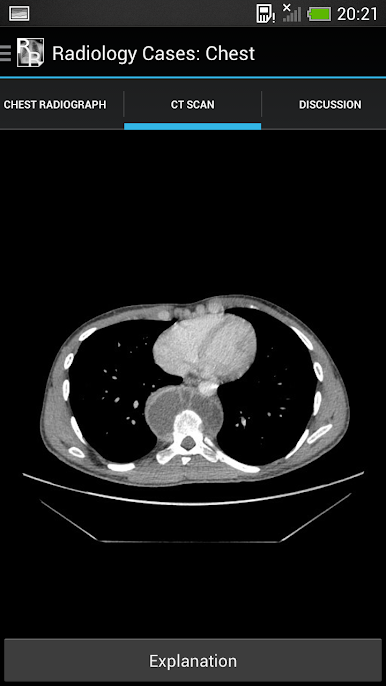

It consists of 26 cases, each with a brief history and a chest x-ray. The user should try to interpret each chest x-ray before revealing the explanations at the bottom of each page.

The aim is to gain an understanding of the basic principles of chest x-ray interpretation and specific radiographic features of common diseases. The diseases encountered are discussed along the way and many of the cases have a scrollable

CT to help with understanding the chest x-ray appearances.